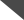

48岁女性,既往有高血压,糖尿病,高脂血症,近期髓系白血病急性变行尼洛替尼化疗,本次表现为意识状态改变,左上肢无力,恶心呕吐,推测可能为卒中。大约12小时前,患者完全正常。查体提示患者思睡,对自身病史不能很好回忆。时间,姓名回答正确,能遵嘱动作。存在构音障碍。右侧肢体肌力5级,左侧肢体2级伴左侧面瘫。CT提示右侧额颞叶高密度,像出血的卵圆形肿块(图1)。MRI证实右侧大脑凸面4.7×2.7cm附着于硬脑膜的强化病灶(图2)。

(图2:A:T1增强提示右侧额颞叶附着于硬脑膜的4.7×2.7cm强化病灶;B:T2WI提示明显的血管源性水肿伴中线移位和脑室受压变形;C:DWI上病灶呈高信号)